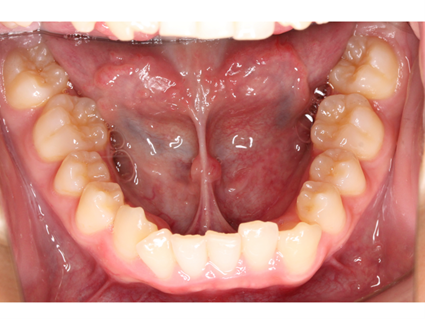

前歯のみの治療、すきっ歯、出っ歯になっている歯、下の歯だけなど、ご希望に合わせた部分的な治療ができます。